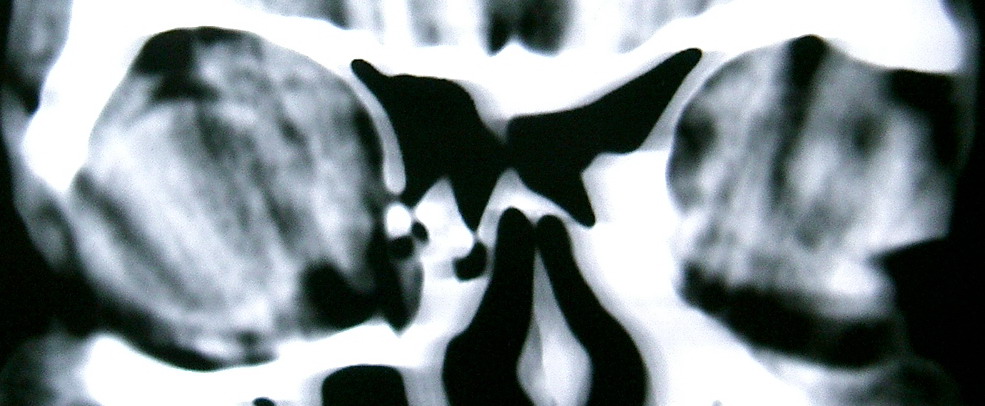

眼眶冠扫,平扫CT: 左眼球内上方可见不规则软组织块影,大小约2.5*1.0CM,与邻近组织分界不清,相邻之内直肌、上直肌增粗,眼环正常,眶壁骨质无破坏,左上颌窦底部可见粘膜增厚,其余副鼻窦未见异常。 IMP:1,左眼眶肿物;2,左上颌窦炎